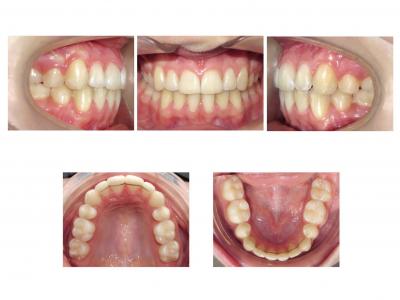

Voici les deux patientes traitées

Ici, dans les deux cas, les deuxièmes prémolaires ont été extraites et les traitements ont duré 18 mois.

Dans le deuxième cas, le désencombrement a fermé les espaces en 6 mois. Les incisives ont été surtorquée pour avoir un meilleur soutien labial. Le traitement qui avait bien débuté, a été difficile à finir, car les anatomies coronaires et radiculaires étaient perturbées.